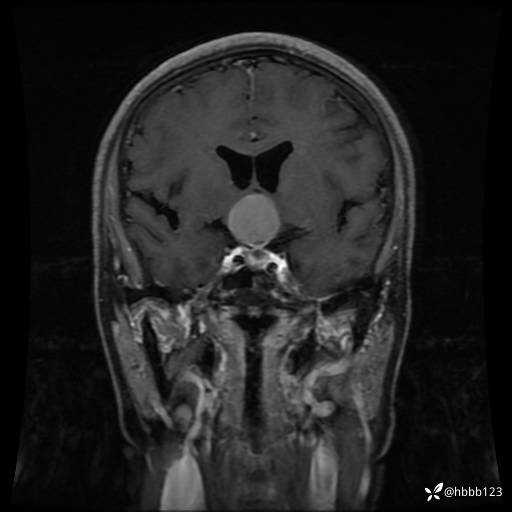

T1WI 增强 矢状位重建: